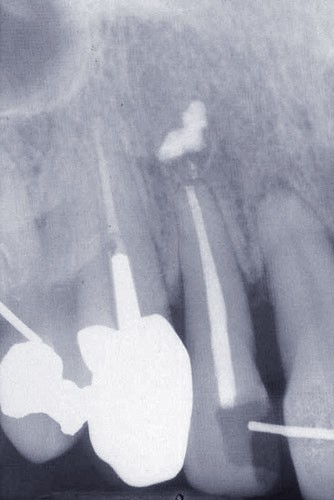

Une patiente âgée de 45 ans consulte à la fin des années 1990 avec une contention en échelle au maxillaire afin de soulager les mobilités des dents antérieures.

Les examens cliniques et radiographiques montrent une parodontite chronique généralisée (fig. 1a à m).

Nous décidons d’entreprendre une thérapeutique initiale parodontale classique dans tous les secteurs, y compris l’extraction de 24, un bridge de 45 à 48 avec 46 en pontique, un bridge complet de contention de 17 à 27 sur 11 piliers dentaires et une greffe épithélio-conjonctive sur 31. Cette dernière ne sera jamais réalisée. Le bridge maxillaire permettra de réduire le surplomb antérieur et d’améliorer le sourire de la patiente, ce qui constitue l’une de ses demandes.